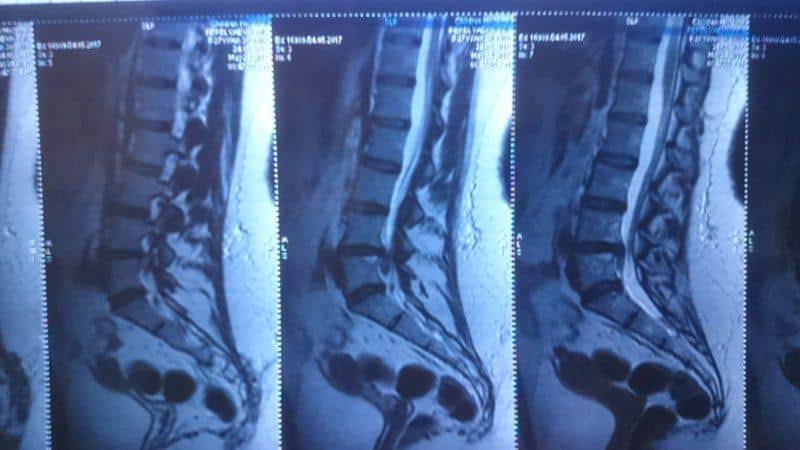

- МРТ. Данный метод позволяет подробно исследовать спинной мозг и межпозвонковые диски.